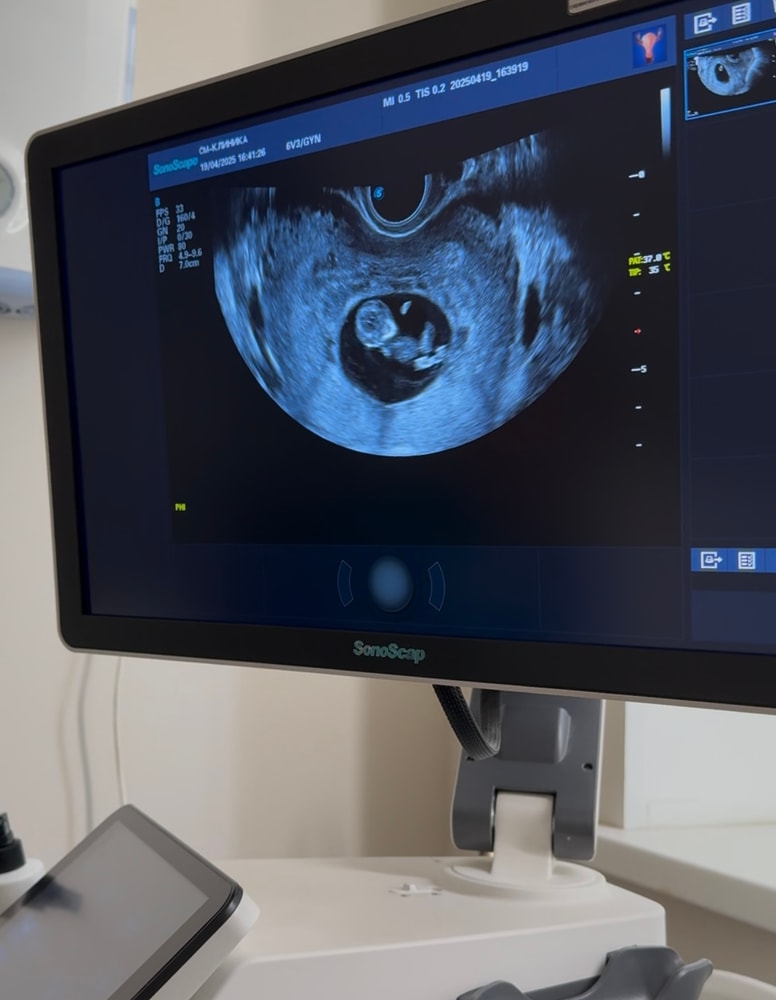

То, во что нам верится с трудом после замершей.

наше чудо. Счастье. Огромная любовь сегодня заставила своих родителей смеяться и плакать от положительных эмоций. Мы видели твои движения. Малыш, ты такой юркий и активный. Я жду не дождусь твоих пиночков.

срок 10,2, но по узи на пару дней опережаем 🥹